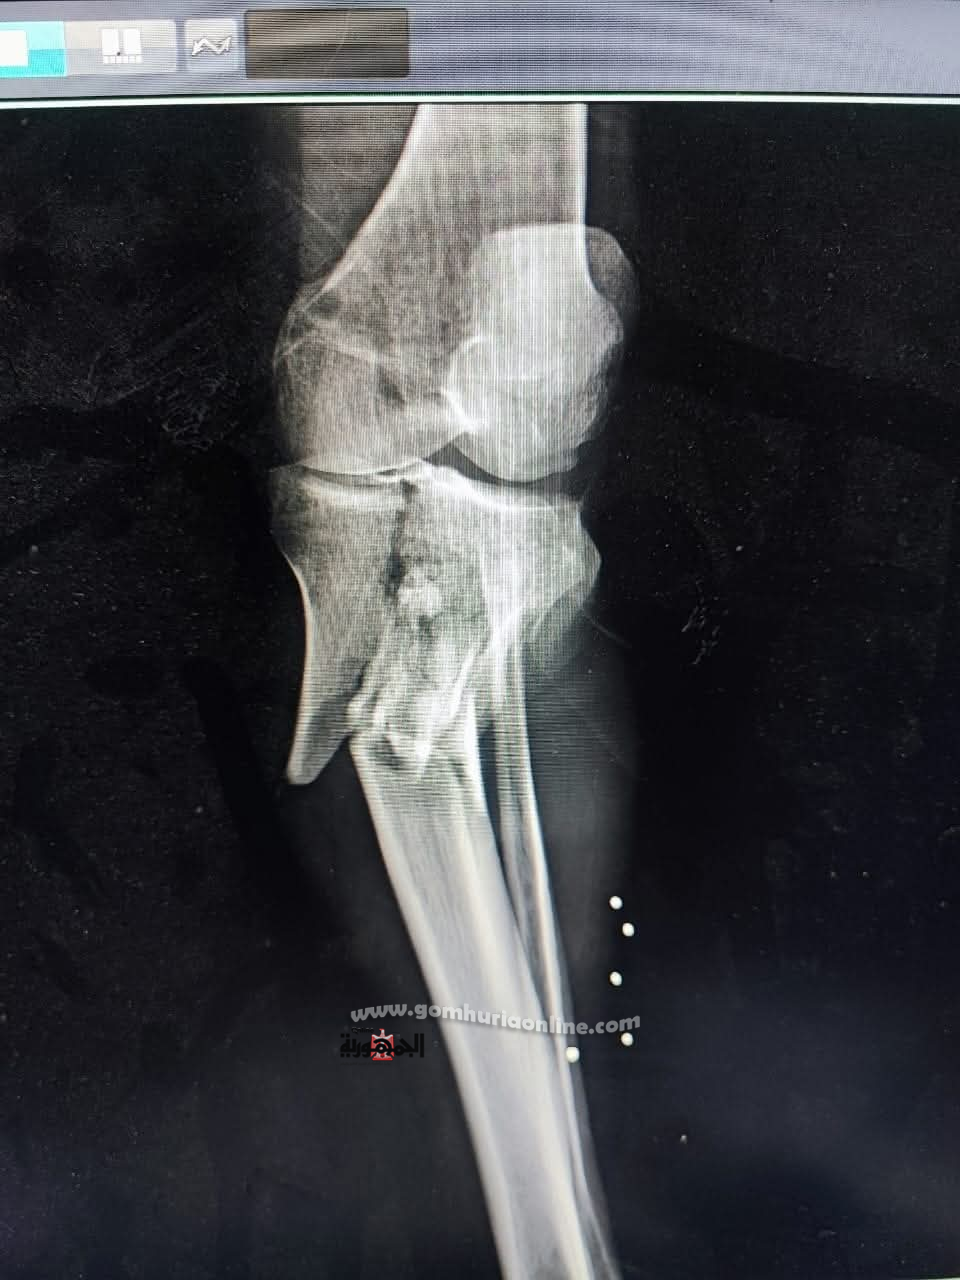

أعلن الدكتور شادي عبده مدير مستشفى الصدر بالمنيا بانه بناء على توجيهات الدكتور خالد عبد الغفار نائب رئيس مجلس الوزراء ووزير الصحة والسكان واللواء عماد كدواني محافظ المنيا والدكتورة نادية مكرم وكيلة وزارة الصحة بالمنيا شهدت  مستشفى صدر المنيا  اليوم نجاحًا طبيًا باهرًا تمثل في إجراء عملية جراحية دقيقة لتثبيت كسر مفتوح ومفتت من الدرجة السادسة بالركبة لمريض يبلغ من العمر 58 عامًا.

أُجريت العملية في تمام الساعة الواحدة صباحًا، وتكللت بالنجاح بفضل جهود ومهارة الفريق الطبي المتكامل وقد استخدم الفريق الطبي تقنية إليزاروف المتقدمة، بالإضافة إلى المسامير، لتثبيت الكسر المعقد، مما يمثل خطوة مهمة نحو تعافي المريض.